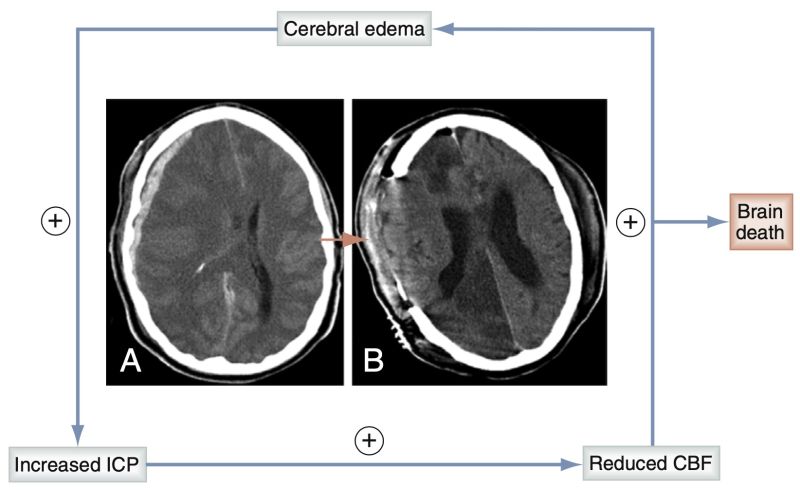

After severe head injury with intracranial pressure (ICP) elevation, a positive feedback loop can ensue, leading ultimately to brain death. This situation can be likened to a compartment syndrome within the noncompliant skull. Elevation of ICP (A) impedes cerebral blood flow (CBF). This leads to ischemia (B, which illustrates an extreme case with strokes in the right anterior and posterior cerebral artery distributions as a consequence of cerebral herniation), which leads to cytotoxic edema caused in part by adenosine triphosphate–dependent Na+-K+ pump failure. This in turn further increases ICP and decreases CBF. This situation can ultimately progress to brain death if ICP becomes so high that the cerebrum is not perfused, as seen on an angiogram.